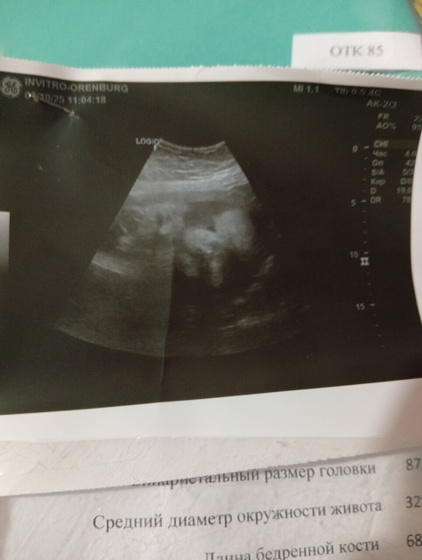

Приветик всем съездила я на узи ещё раз переживала что шевеления сильные очень. Но с малышкой все хорошо выглядит на 35-36 недель, хотя у меня сейчас 33 недели. Вес поднабрала дочь 2830, и самое главное перевернулась. и дату пдр теперь по узи на 4.11.25 начало месяца. Даже показала своё личико😍😍